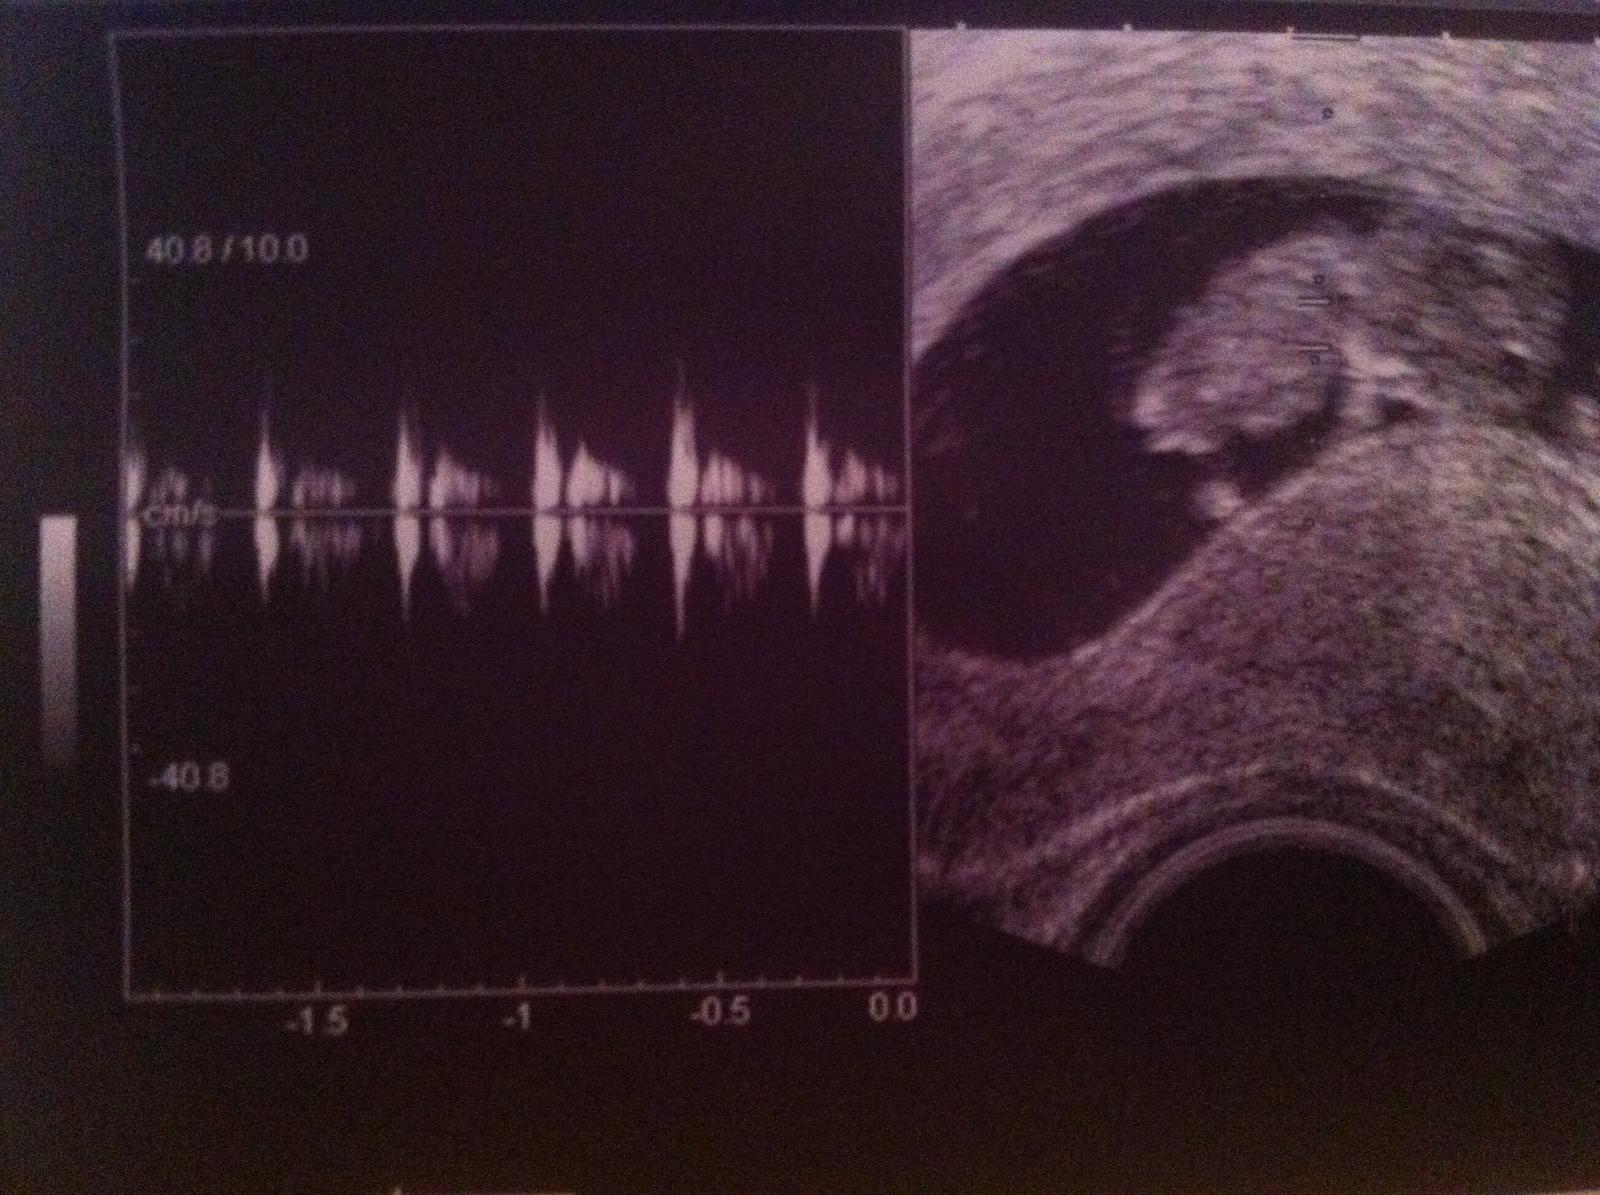

Babulky babulky rastie ma 2,9 cm,som taka stastna.dostala som knizku,takze pripajam Foto drobatka.hadam bude dobra kvalita fotky

@bokroska som 9+4drobatko je o den mensie,ale to hadam dozenieme..

@gorka no tak opat... 29mm je rozmer na 9+5tt, takze opat neviem, cim sa riadi tvoj lekar 😅

ale teda den hore dole NIE JE ziadne meskanie ani predbiehanie, to sa ani neberie do uvahy, nema co dohanat 😉

ani 4dni hore dole sa nerataju za meskanie alebo predbiehanie - akekolvek plus/minus v ramci jedneho tyzdna je absolutne v poriadku a absolutne nic to neznamena, to su milimetrove udaje, ktore mozu byt skreslene hoci aj nepresnostou merania - ved ako tam ten lekar cvakne barskam, ked meria - od oka, naozaj tie milimetre NIC neznamenaju 😉

ono sa za presne meranie povazuje az NT screening, ktory sa robi medzi 12-14tyzdnom - vtedy sa uz podla velkosti stanovuje aj realny termin porodu, nakolko vsetky udaje dovtedy, vratane utz a terminu podla ms su LEN orientacne 😉